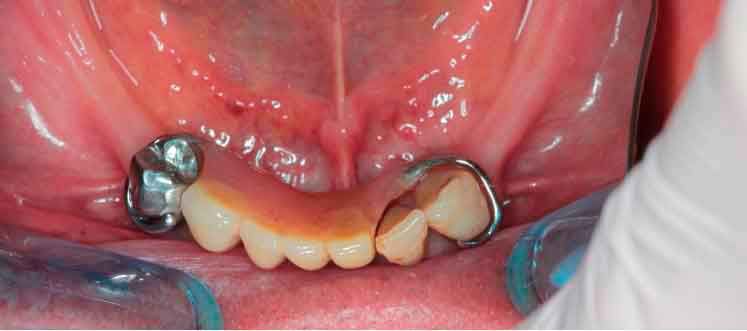

Picture - Initial bite situation

In a typical digital workflow, the first step involves intraoral scanner (IOS) acquisition. However, in cases with insufficient references, obtaining an accurate bite can be challenging. Discover alternative methods to construct dynamic virtual patients, bridging the gap from initial situations to provisional solutions.

Before acquiring the CBCT, I added 2 pieces of composite to the mandible to be able to do the picking process during jaw motion recording. This is a useful trick to remember in a situation of lacking teeth.